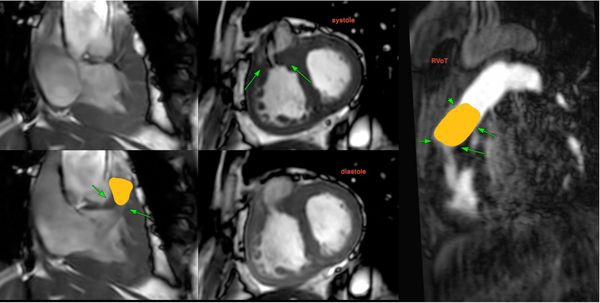

COD 158 - Septum Predominant HCM and RVoTo

RVoTo involvement in HCM is uncommon but diagnosing it may change the management plan and prognosis